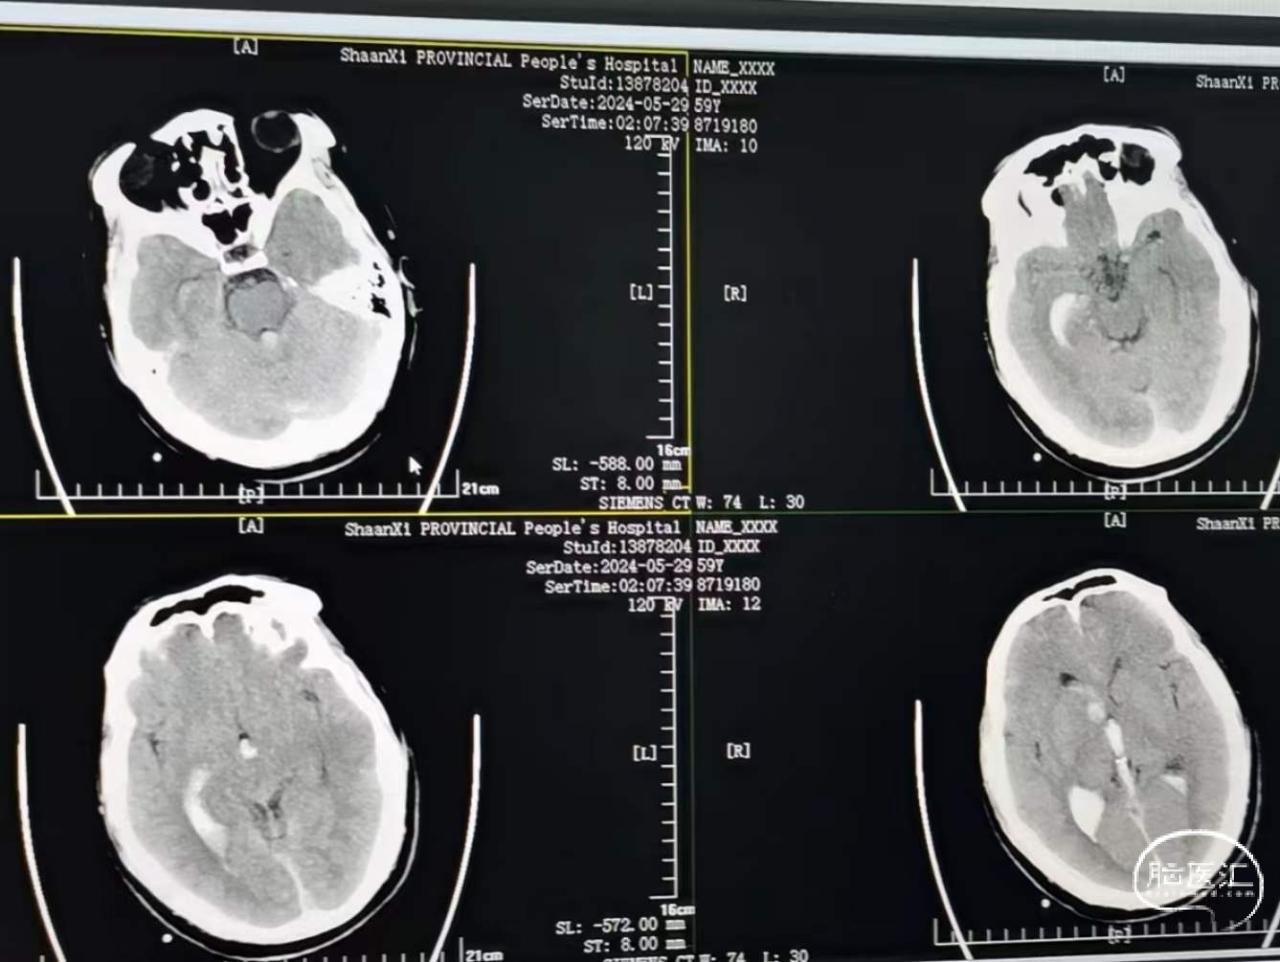

当地发现脑出血破入脑室,钻孔引流以后发现出血增加。查CTA发现有血管畸形,位于脑干旁边,有大脑后及脉络丛参与供血,急诊开颅,切除畸形并清除血肿。

畸形血管团,毗邻刚才所说的基底动脉、脑干、滑车神经、动眼神经,破裂出血。